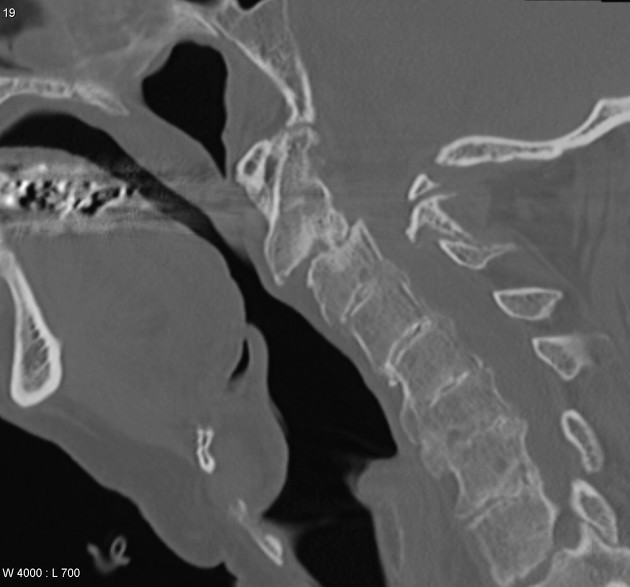

cervical spine is involved in what percentage of RA pts?

70%

Common association of RA in the cervical spine

atlantoaxial subluxation: - anterior: laxity of transverse ligament - vertical (atlantoaxial impaction): odontoid through foramen magnum secondary to facet erosion and collapse - posterior: due to odontoid fx

dens involvement in RA